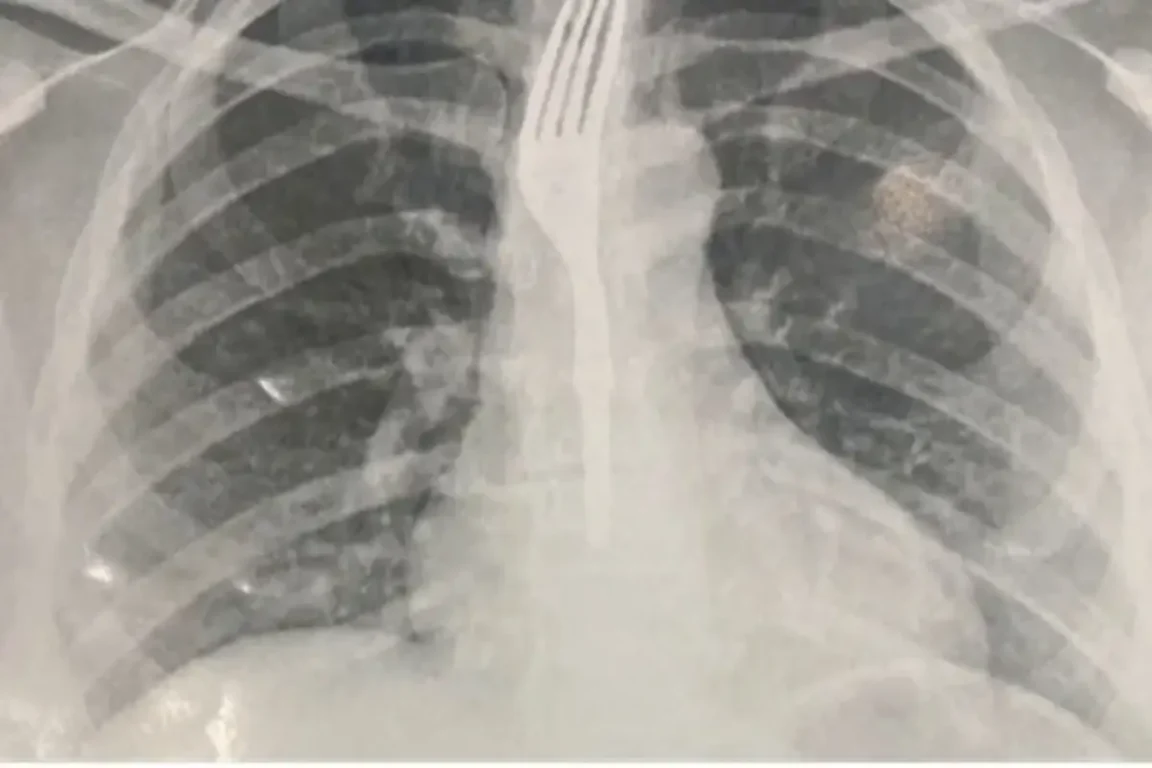

Ela foi levada ao Hospital Geral de Guanambi (HGG), onde exames de imagem indicaram que o utensílio estava alojado no esôfago.

Segundo o site achei sudoeste ,ela foi levada ao Hospital Geral de Guanambi (HGG), onde exames de imagem indicaram que o utensílio estava alojado no esôfago, em posição de risco.